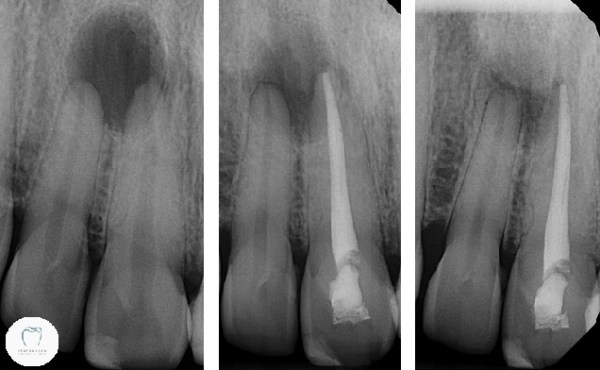

Both teeth are badly discoloured and heavily filled. His upper right central (red dot) tooth was hurting. A lot. If we tapped on it, there was even more pain. So we took an X-ray and found this:

You can see the great big black circle above and around the roots of two teeth. That’s an abscess. Now the question becomes “One tooth or two?” Looking at this X-ray, I’d say two teeth are compromised.

Having cleaned out the dead nerve and completed the root canal treatment in just the central tooth, we wait. Here’s the sequence of x-rays showing what happened over the year:

Well, you should be able to see for yourself what’s happened here. The big dark open hole in the bone has almost completely filled in. It certainly appears that the single root canal treatment is successful. There’s still some risk that I’ll end up having to root treat the other tooth too, but hopefully not. (The patient of course is fully aware of this)